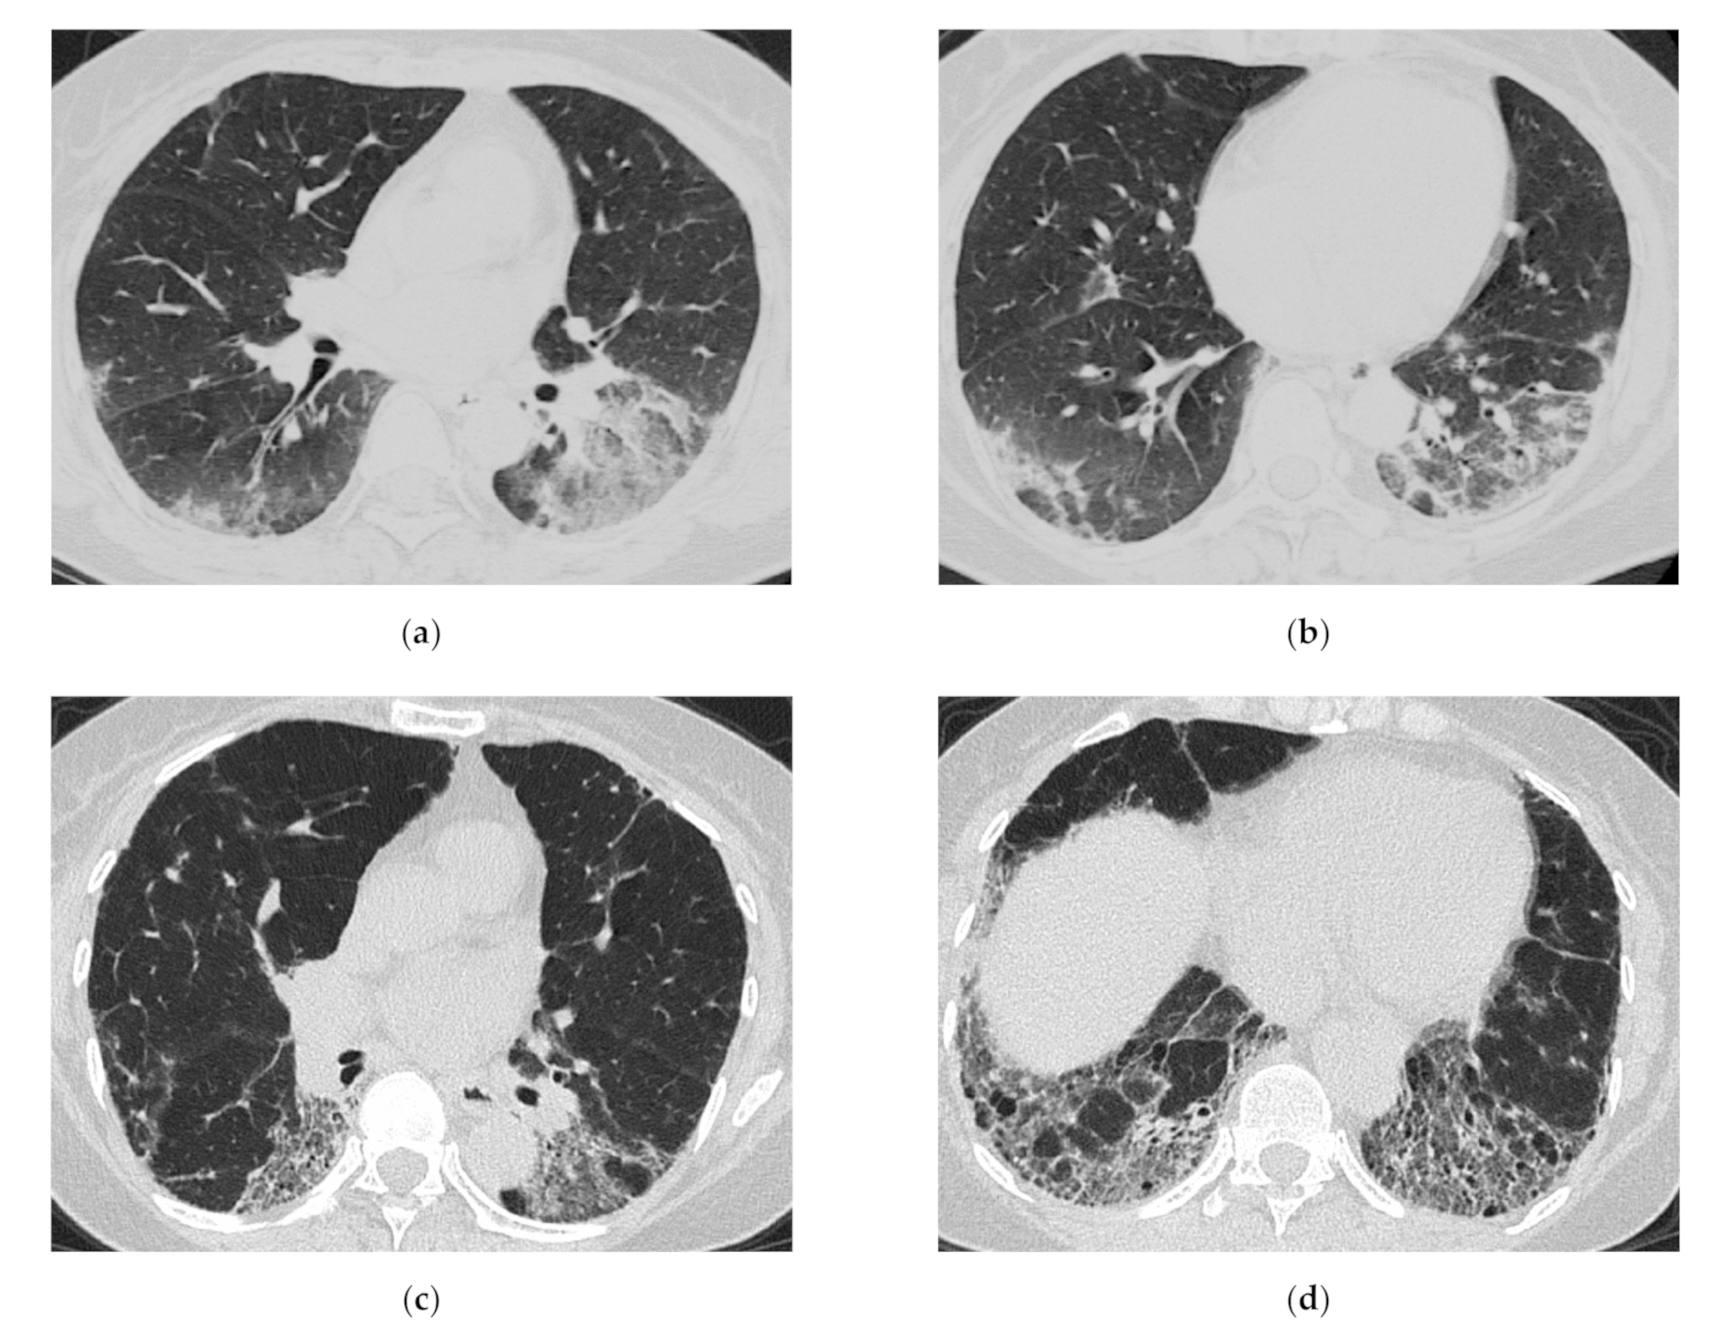

2. HRCT Features of Myositis Spectrum Disease-Related ILD Based on Clinical Course

4. HRCT Findings in Relation to the Poorer Prognosis

5. Clinical Pearls from HRCT Findings